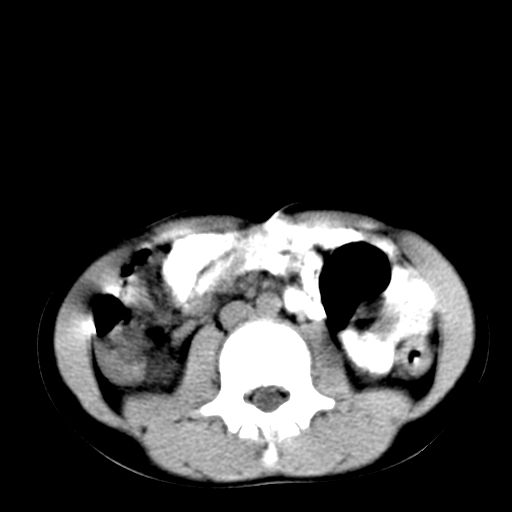

腹部好象未见异常。

腹部ct平扫未见明确异常

腹部ct平扫不能提示哪里有病变。